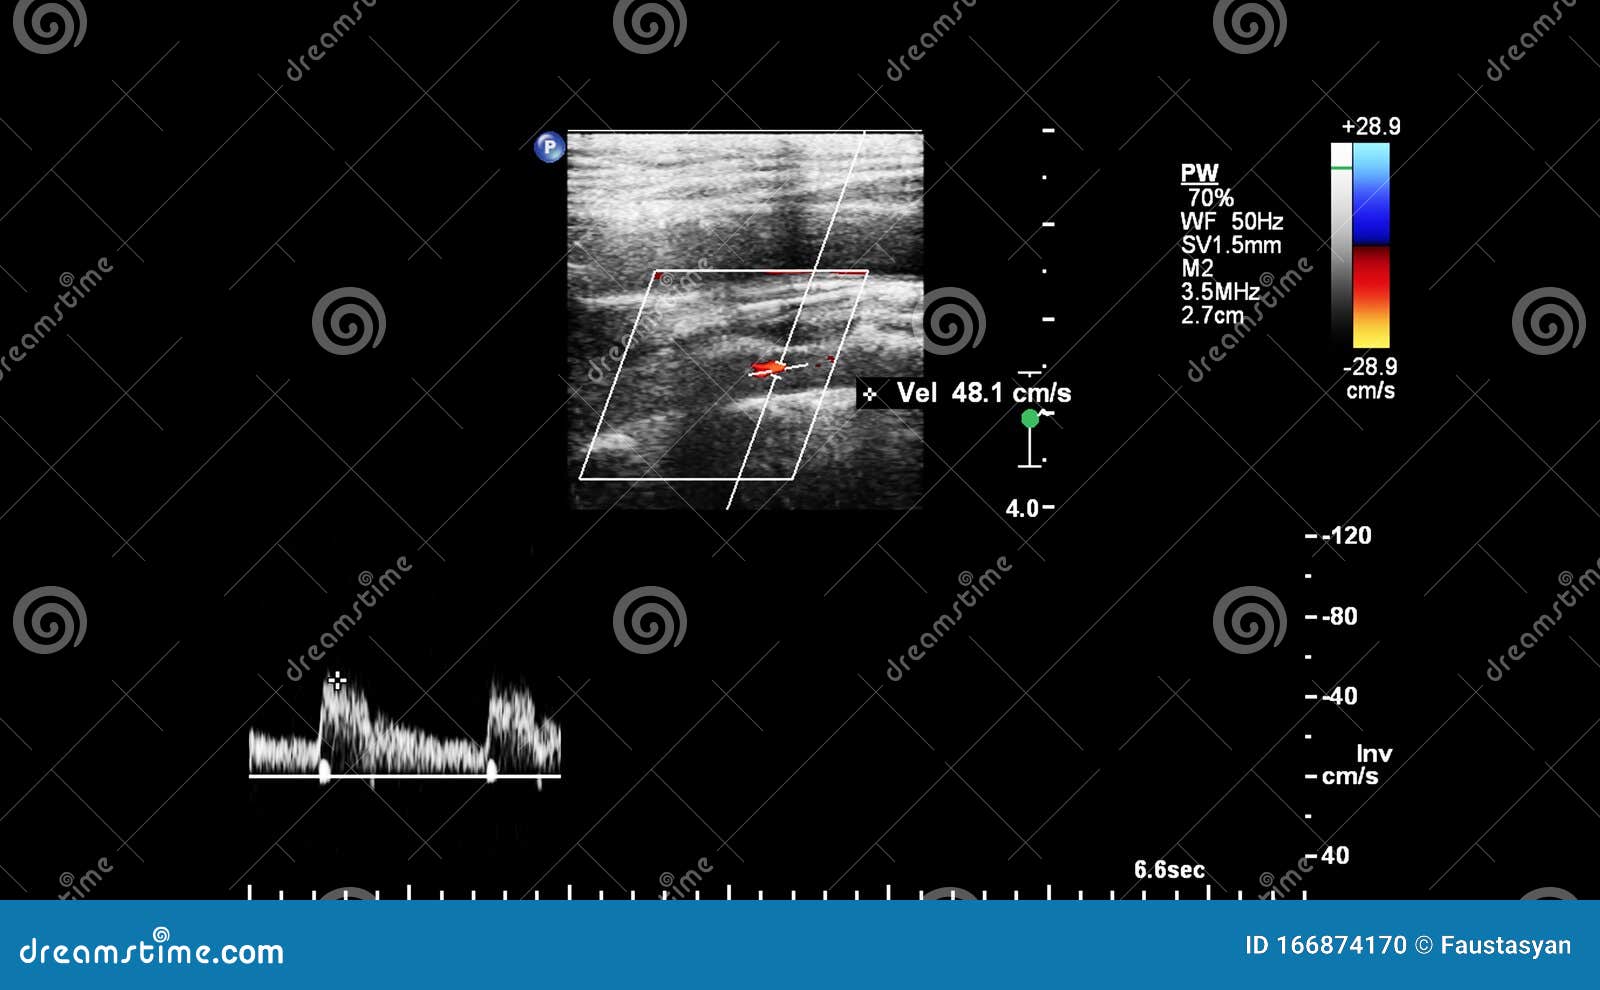

Pulse Wave Doppler Ultrasound Examination. Stock Photo Image of patient, cardiology 166874170 Pulse Wave Doppler Ultrasound These represent passive filling of the ventricle (early [e] wave) and active filling with. Measure blood flow velocity to understand disease states. Medical doppler ultrasound is usually utilized in the clinical adjusting to evaluate and estimate blood flow in both the. Pulsed wave doppler (pwd) uses discontinuous pulses. Pulsed wave (pw) doppler uses the doppler principle that moving objects change. Pulse Wave Doppler Ultrasound.